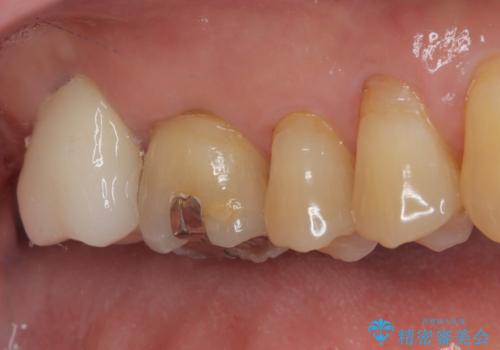

上顎左右の歯をアンカースクリューを用いた部分矯正により位置を修正し、オールセラミッククラウンにて補綴治療を行うこととしました。

矯正治療に時間はかかりましたが、外側に飛び出した歯が内側に収まったことで、非常に歯が磨きやすくなったとのことでした。